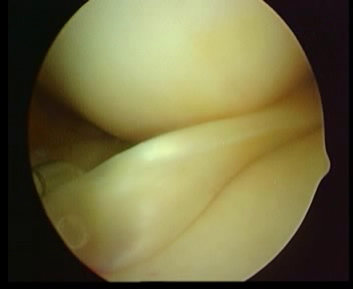

橫裂

瓣裂

水平裂